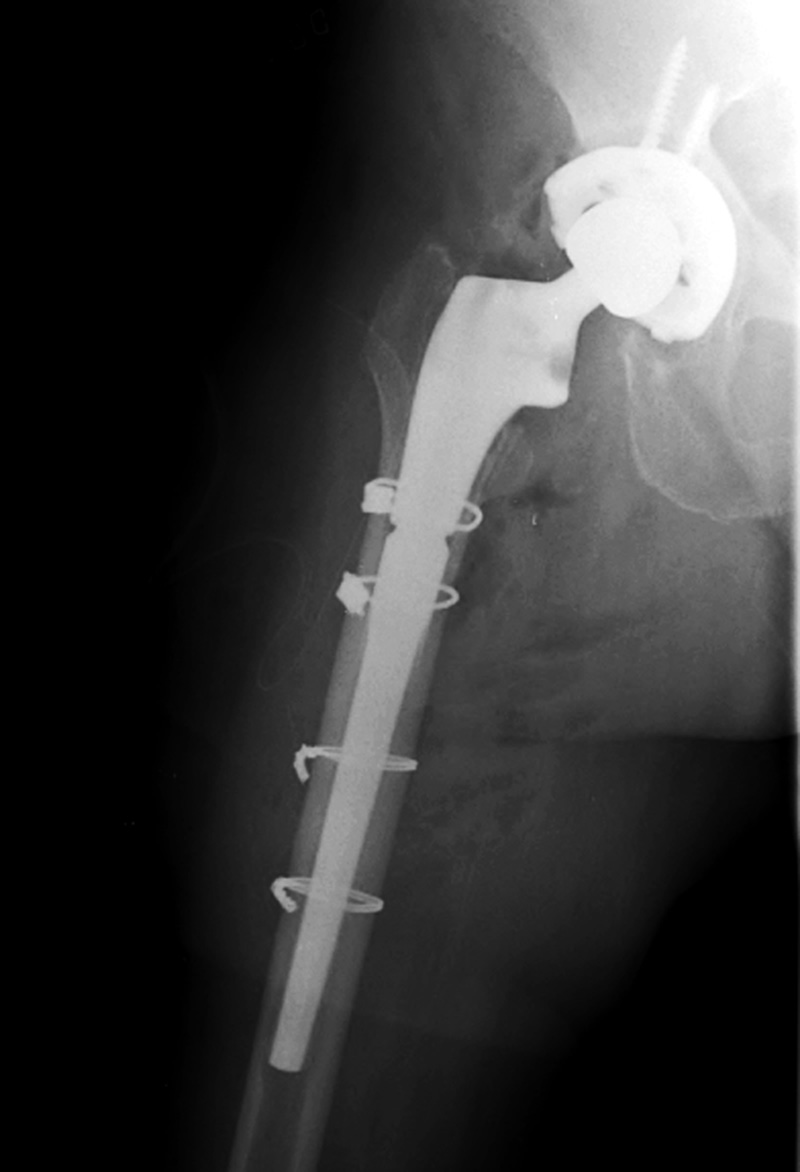

| Total hip arthroplasty with cerclage wires |

| |

The cerclage wires were placed because a femoral shaft fracture (not visible herein) occurred during the prosthesis placement. There is subcutaneous gas from recent placement of the prosthesis. From Taljanovic, 2005 |